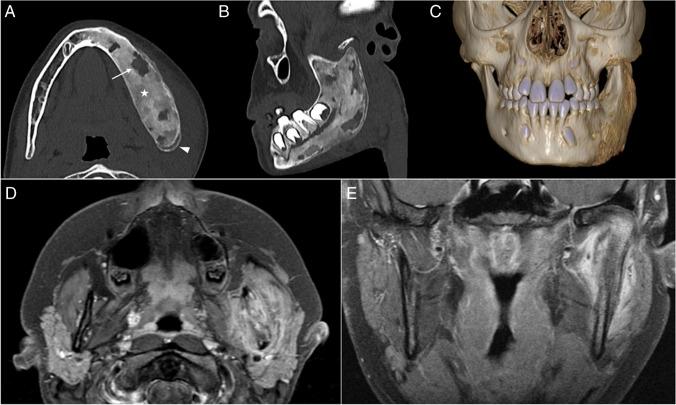

We included 13 patients (six male). The mean age of onset was 12.3 years. Ten patients had only vertebral lesions, two had only mandibular lesions, and one had both. For patients with vertebral lesions, the median number of levels affected was three, 81.8% had multiple levels affected, 90.0% had dorsal spine lesions, 72.7% had platyspondyly, and 81.8% had inflammatory changes. All vertebral lesions had at least partial resolution of inflammatory findings, the mean time of lesion activity was 2.5 years, and recurrence occurred in 27.3%. Three patients had sacral lesions, all with sacroiliitis. In patients with mandibular lesions, all had unilateral lesions involving the mandibular ramus, all had hyperostosis, periosteal reaction, bone edema, and soft tissue inflammation, all had partial resolution on follow-up, and one had recurrence.

CNO vertebral lesions are not rare, are often multiple, predominantly affect dorsal levels, and most result in vertebral height loss. Resolution of vertebral inflammatory lesions is frequent, but so is recurrence. Sacral lesions may be present and result in sacroiliitis. The mandible may be a site of unifocal disease, typically affecting the ramus, with prominent bony changes and soft tissue inflammation.

共纳入 13 例患者(男 6 例),平均发病年龄为 12.3 岁。10 例患者仅存在脊柱病变,2 例仅存在下颌病变,1 例同时存在两种病变。存在脊柱病变的患者中,受累椎体数中位数为 3 个,81.8%的患者存在多个椎体受累,90.0%的患者病变位于胸椎,72.7%的患者存在扁平椎,81.8%的患者存在炎症改变。所有脊柱病变均有不同程度的炎症改变缓解,病变活动的平均时间为 2.5 年,27.3%的患者复发。3 例患者存在骶骨病变,均伴有骶髂关节炎。存在下颌病变的患者中,病变均位于下颌骨升支,均表现为骨增生、骨膜反应、骨水肿和软组织炎症,随访时均有不同程度的缓解,1 例复发。

CNO 的脊柱病变并不罕见,常为多发病变,主要累及胸椎,且多导致椎体高度丢失。脊柱炎症性病变常可缓解,但也易复发。骶骨可能受累,导致骶髂关节炎。下颌可能为单发病变的部位,典型表现为升支受累,有明显的骨改变和软组织炎症。